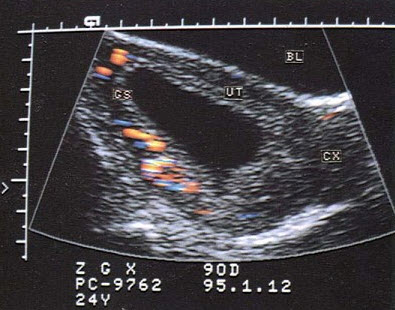

20、单项选择题

女,26岁,停经3个月,HCG阳性。根据B超检查声像图如下,最可能的诊断为()

A.葡萄胎

B.子宫肌瘤

C.稽留流产

D.不全流产

E.绒癌